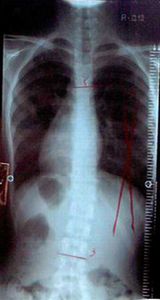

症例12)

初診18歳でも体操で大きく度数の改善と身長も2センチ伸びた。

�@平成19年4月初診 18歳 男子受験生

14度-25度 身長168センチ

�A平成20年8月 医学部学生となっており、改善しお礼に来院。

12度-14度 身長170センチ・成人として安全度数です。体操の継続により受験を突破し改善と身長も伸びた。終了です。

彼は改善と身長が伸びたことを大変喜んでいました。

君が整形外科医になったらどうすると質問すると私は自分で体験しましたので体操を指導しますと話してくれました。

平成19年4月

初診レントゲン

平成20年8月

レントゲン

(14度)-25度

12度-14度